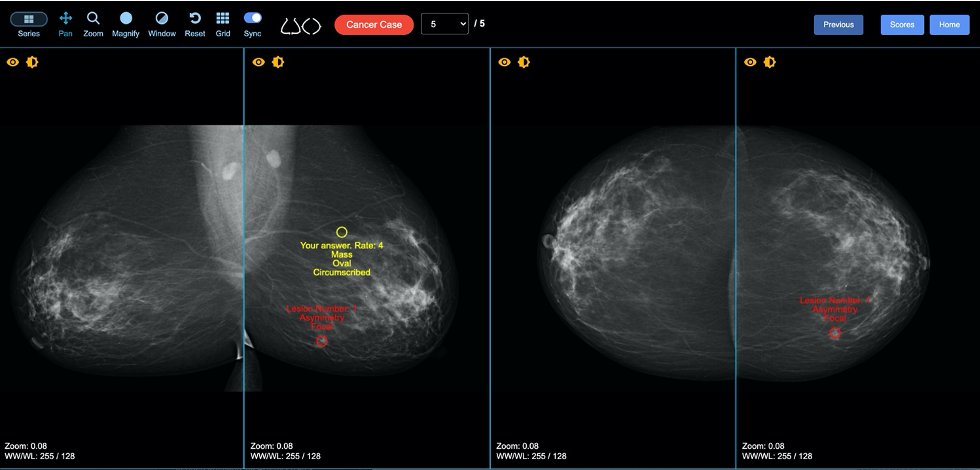

Moderately/severely symptomatic patients: CXR is often negative early, only to turn positive subsequently. The most characteristic findings are basilar and peripheral ground-glass opacities (GGOs) (Fig. 1).

Unfortunately, only a minority of patients have this typical COVID-19 pattern. In most patients, the disease is located more diffusely or elsewhere. Consolidation may be present initially with more severe illness or duration (Fig. 2).

Early on, CT may be positive when the CXR is negative. The typical GGO distribution is similar, but usually more extensive than on CXR (Fig. 3).

Adenopathy, cavitation, and effusion are uncommon early on. Compared to other viral pneumonias, peripheral lower-lobe GGOs are more common in COVID-19, whereas other pneumonias tend to have more diffuse disease. There is considerable overlap, however.

Reporting guidelines: Many templates have been proposed. Radiological Society of North America guidelines (Radiology: Cardiothoracic Imaging, Vol. 2, No. 2) define:

- CXR = negative, COVID-19-like; regular pneumonia, other disease

- CT = negative, typical of COVID-19; indeterminant, not COVID-19

Both show moderate interobserver reproducibility.